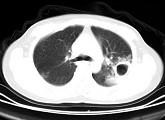

问题 男,25岁,咳嗽,咯血近1周,午后低热1个月余,CT检查如图,最可能的诊断为 ( )

选项 A.畸胎瘤 B.双上肺结核,左上肺结核空洞形成 C.液气胸 D.肺大疱 E.肺炎

答案 B